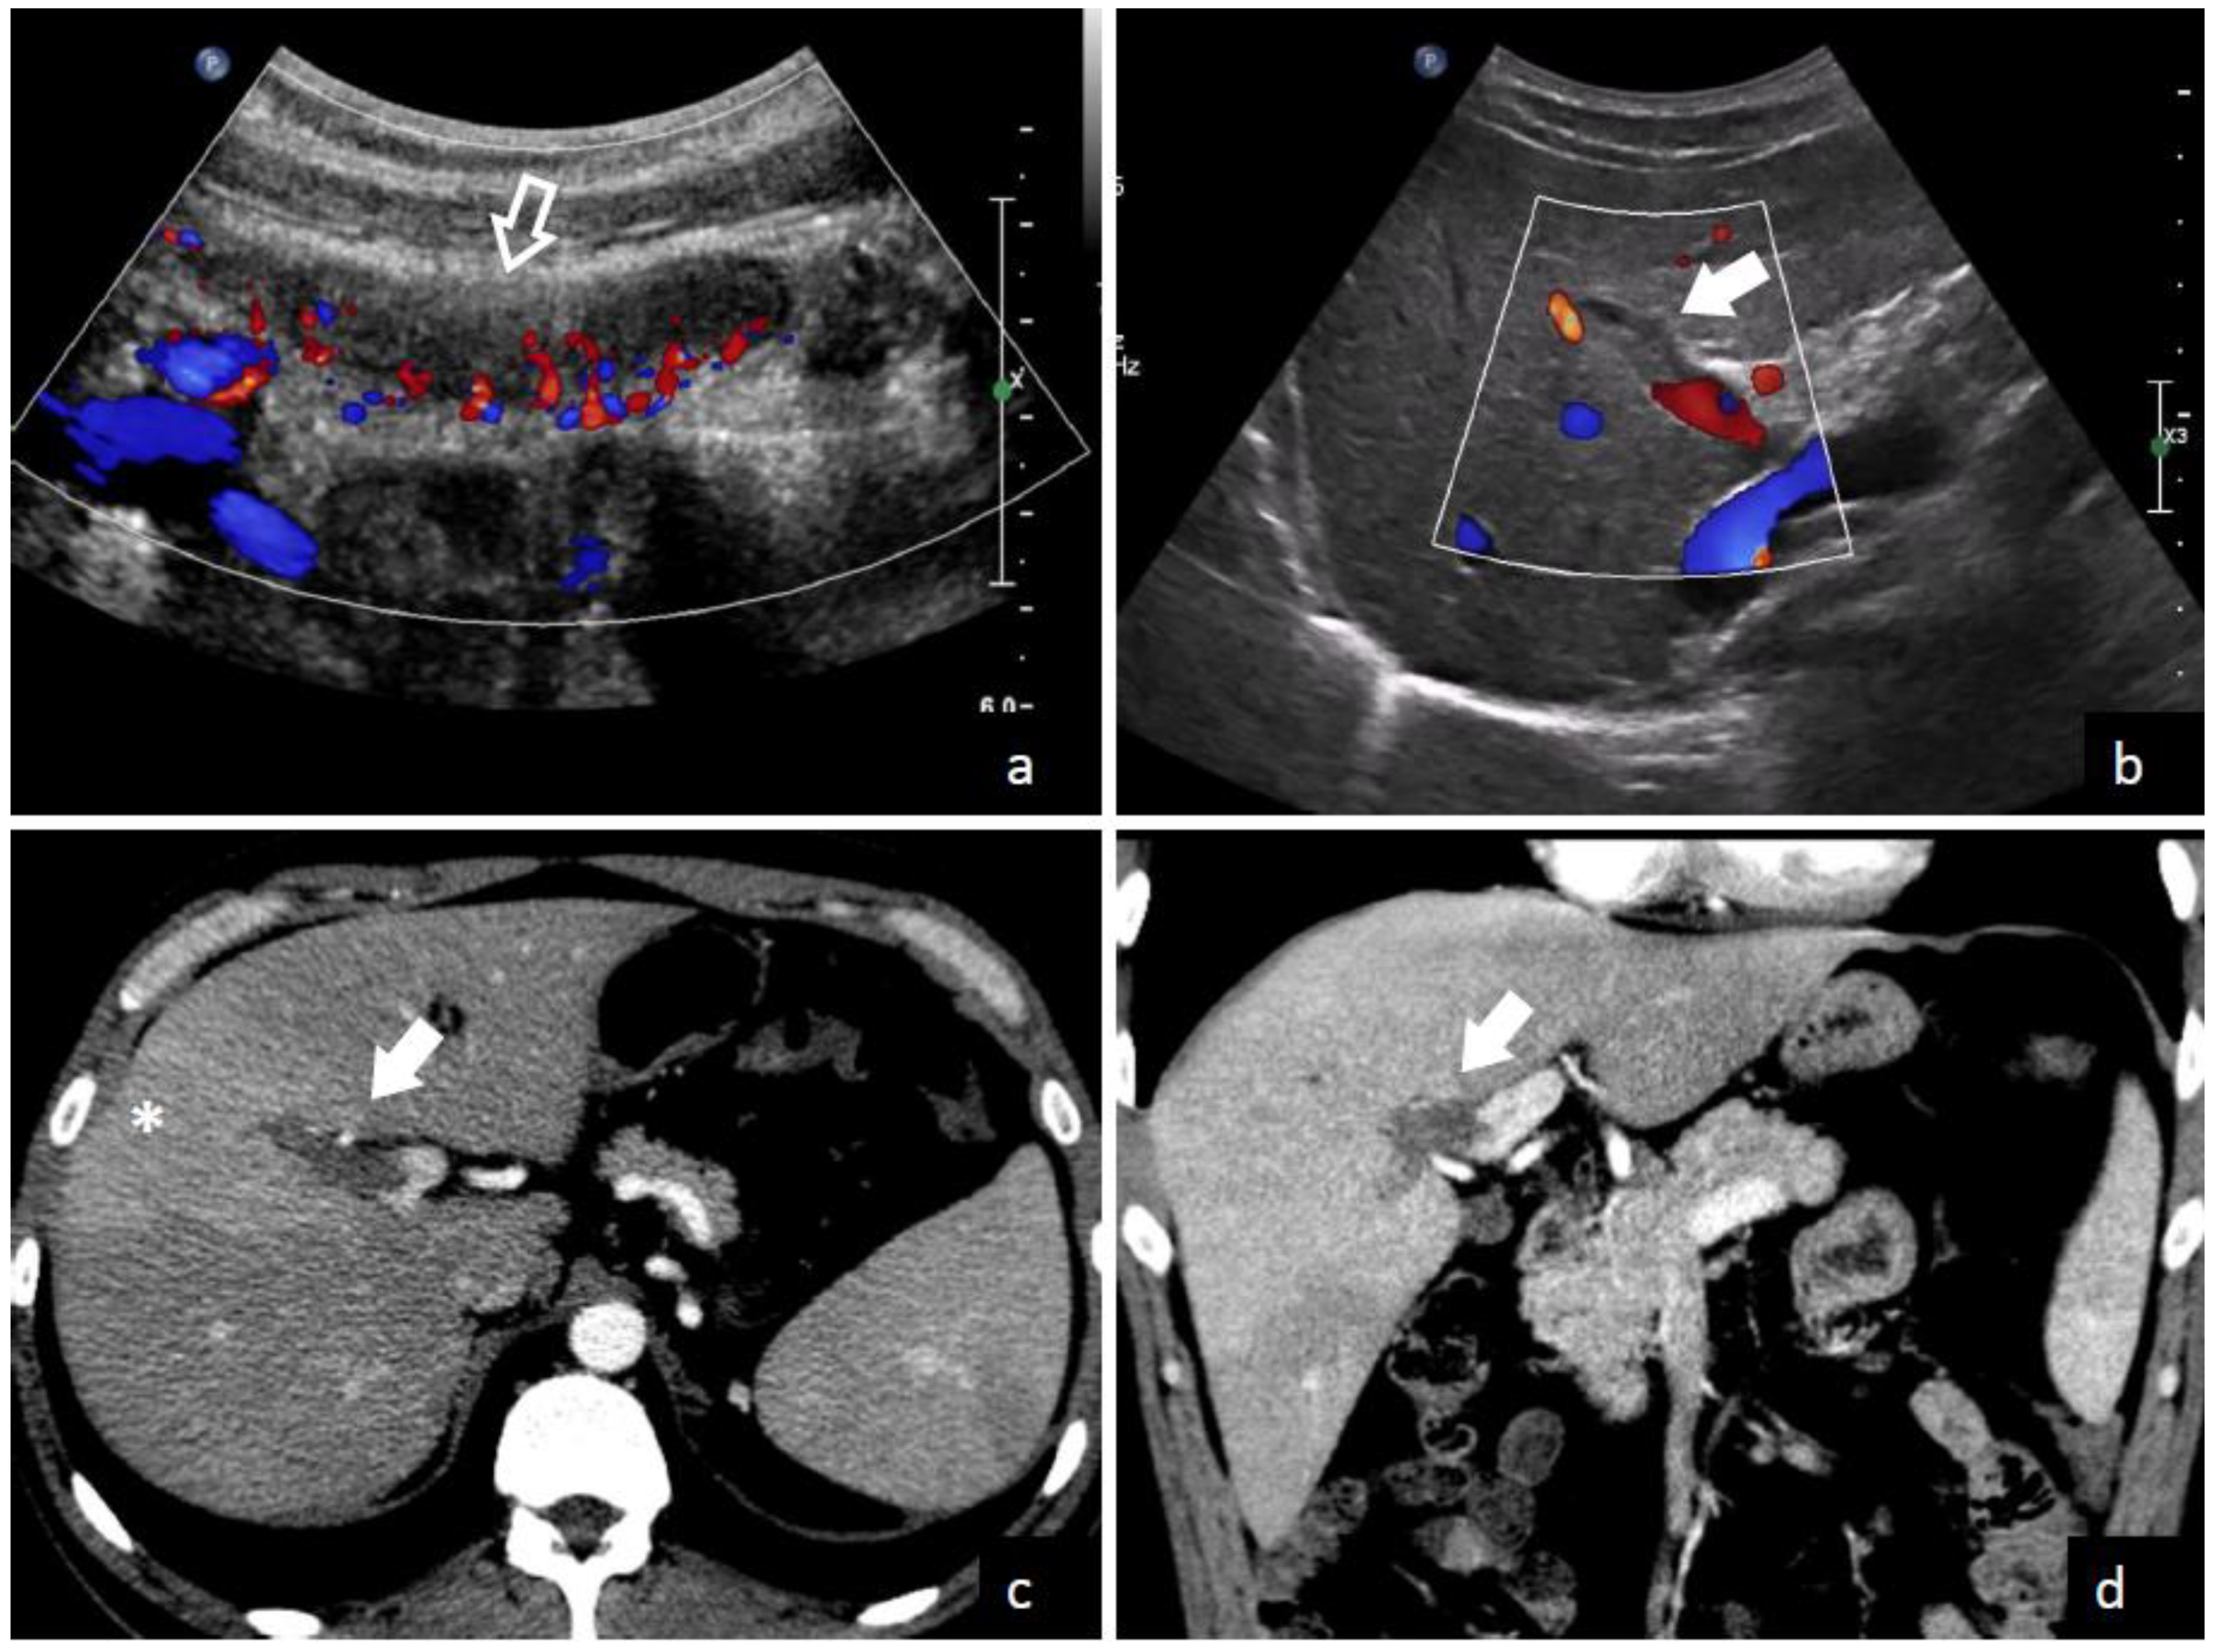

The demonstration of thrombus in the portal vein is the central finding leading to a pylephlebitis diagnosis. Both computed tomography (CT) scanning and abdominal ultrasonography can detect the presence of thrombi in the portal vein as shown in Figure 3 and Figure 4. Ultrasonography can detect the presence of echogenic material in the portal vein lumen, which can be confirmed by flow alterations on Doppler analyses [2,213]. CT scan should be preferred because of its higher definition and the additional investigative ability to identify possible abdominal or pelvic infective foci [2,39,65]. According to a recent systematic review, which enrolled studies between 2010 and 2021, the diagnosis was determined with a CT scan in 89.3% of patients and an ultrasound examination in 38.8% of patients [208]. In contrast, a previous review which included studies before 2010, found that CT scan was used only in 51% of patients. Magnetic resonance imaging (MRI) [44,210], angiography [69,91,217], endoscopic ultrasound [81], or positron emission tomography (PET) [5,42] can also be used to demonstrate portal vein thrombosis; however, their application remains limited to selected cases.

Figure 3.

A 35-year-old male with fever and severe abdominal pain was admitted to the emergency department of Trieste University Hospital. Ultrasound with color flow Doppler images (a,b) shows acute inflammation of the appendix (empty arrow in (a)) and echogenic material inside an intrahepatic branch of the portal vein without color flow signal (solid arrow), due to thrombosis. Contrast-enhanced CT images in axial (c) and coronal (d) plains confirm a filling defect in a right intrahepatic portal vein branch (solid arrows), with transient hepatic attenuation differences—THAD—(* in c) due to hepatic arterial compensatory flow in the corresponding segment.